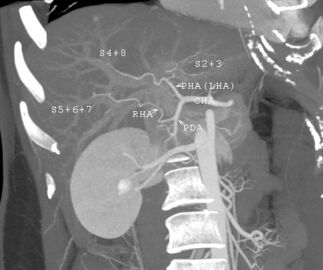

نظام تصنيف كوينو

في نظام كوينو المستخدم على نطاق واسع، تُقسم الفصوص الوظيفية إلى إجمالي ثمانية أجزاء فرعية بناءً على المستوى العرضي من خلال تشعب الوريد البابي الرئيسي.[29] الفص المذنب هو بنية منفصلة تتلقى تدفق الدم من الفروع الوعائية اليمنى واليسرى.[30][31] يقسم تصنيف كوينو الكبد إلى ثمانية أجزاء كبدية مستقلة وظيفياً. كل جزء له تدفق وعائي داخلي وخارجي وتصريف صفراوي خاص به. في وسط كل جزء توجد فروع من الوريد البابي والشريان الكبدي والقناة الصفراوية. في محيط كل جزء يوجد تدفق وعائي خارجي عبر الأوردة الكبدية.[32] يستخدم نظام التصنيف الإمداد الوعائي في الكبد لفصل الوحدات الوظيفية (المرقمة من I إلى VIII) مع الوحدة 1، الفص المذنب، الذي يتلقى إمداده من كل من الفرعين الأيمن والأيسر للوريد البابي. يحتوي على واحد أو أكثر من الأوردة الكبدية التي تصب مباشرة في الوريد الأجوف السفلي.[29] يتم ترقيم بقية الوحدات (II إلى VIII) بطريقة عقارب الساعة:[32]